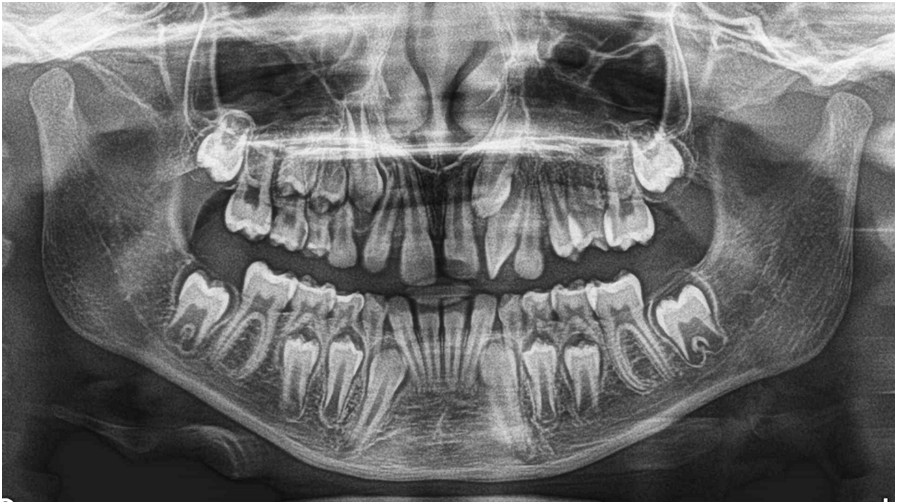

Poniżej przedstawiono zdjęcie pantomograficzne 9-letniej dziewczynki. Jaką diagnozę wstępną (klasyfikacja wg Peck L. et al.) można postawić na podstawie tego rentgenogramu?